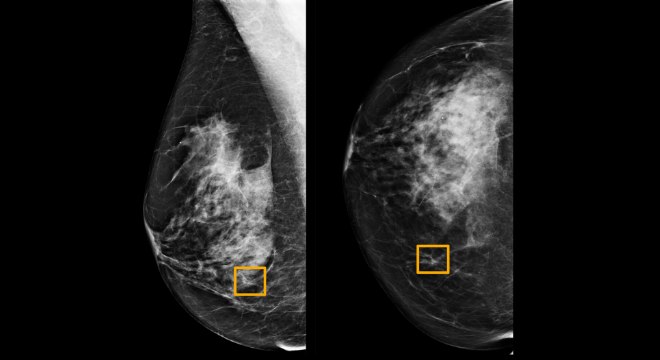

Radiologistas tendem a não detectar cerca de 20% dos casos de câncer de mama Northwestern University/Divulgação via Reuters

Um sistema de inteligência artificial do Google se mostrou eficaz como um radiologista experiente ao detectar que mulheres tinham câncer de mama com base em exames de mamografias, representando uma promessa de melhora na redução de erros, afirmaram pesquisadores nos Estados Unidos e Reino Unido.

A equipe de pesquisadores, que inclui cientistas do Imperial College London e do Serviço Nacional de Saúde do Reino Unido, treinaram o sistema do Google para identificar câncer de mama em dezenas de milhares de mamografias.

Eles então compararam a performance do sistema com os diagnósticos dados aos exames, formados por um conjunto de 25.856 mamografias realizadas no Reino Unido e 3.097 realizadas nos Estados Unidos.

O estudo mostrou que o sistema de IA do Google conseguiu identificar casos de câncer com um grau similar de precisão atribuído a radiologistas experientes. O sistema conseguiu também reduzir o número de resultados falsos positivos em 5,7% no caso dos exames norte-americanos e em 1,2% no caso dos exames britânicos.

A tecnologia também reduziu o número de falsos negativos, que ocorrem quando os exames são diagnosticados erradamente como mostrando normalidade. A redução foi de 9,4% no caso do grupo de exames feitos nos EUA e em 2,7% no caso britânico.